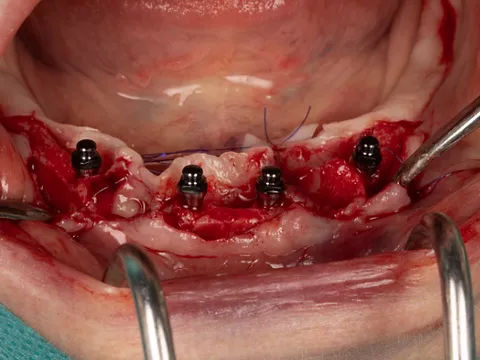

3c. Two mini-implants with a diameter of 2.6 mm and a length of 12 mm were placed in positions 32 and 42, first manually and then using a contra-angle. The insertion torque recorded at the end of the procedure was 21 N.cm in 32 and 17 N.cm in 42. The implants were positioned 0.5 mm subcrestal, i.e. with slight burial of the smooth neck.

3c

3d

3d. Two mini-implants with a diameter of 2.6 mm and a length of 12 mm were placed in positions 34 and 44 using the same protocol as for the previous mini-implants. The torque obtained was 27 Ncm in 34 and 37 Ncm in 44.